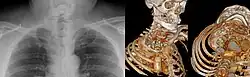

| Srb's anomaly. X-ray and CT scan as volumen rendering | |

Srb's anomaly is the clinical condition describing synostosis, or fusion, between the first and second ribs.[1][2] It may be either a partial or complete fusion between the two ribs to create an entirely indistinguishable new rib.[3]